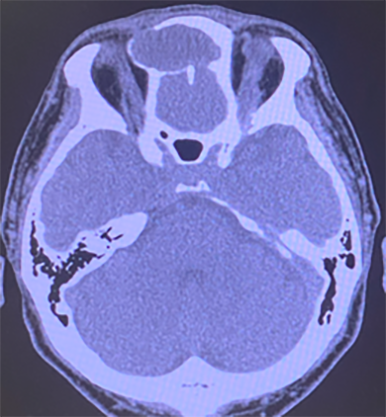

右上顎洞癌(副鼻腔造影Axial CT)

造影Axial CTにて右上顎洞は、腫瘍にて充満し、上顎洞内側壁の破壊あり。